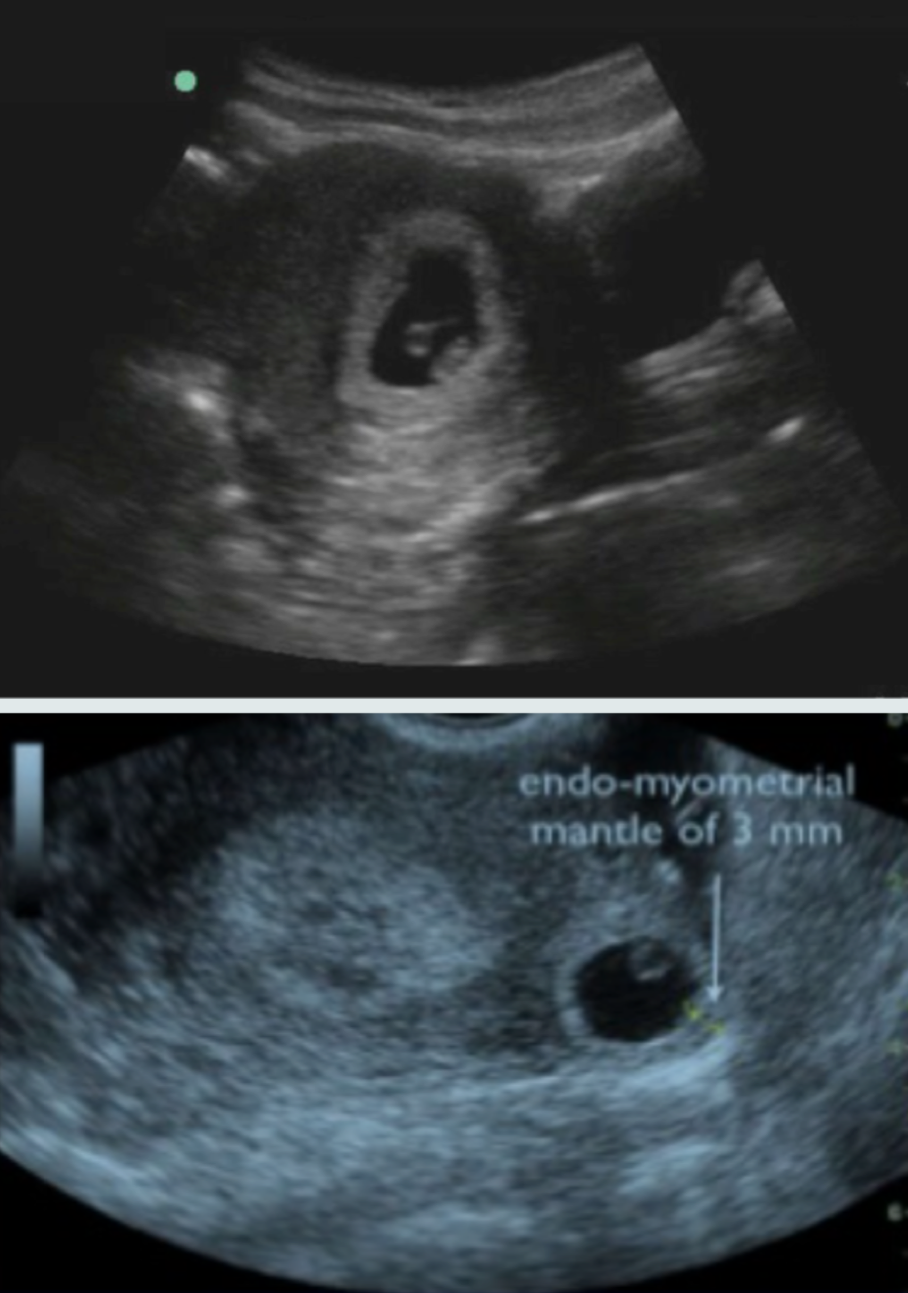

The yolk sac is a circular echogenic ring with an anechoic center seen eccentrically not in the center in. This is because a filled womb will get the baby pushed up which in turn will give a better view of the embryo. This may sometimes be acc. We went in for our 7 week ultrasound and found out our baby was ectopicnothing can prepare you for that. Ultrasound as the initial step in the evaluation of all women presenting to the ED in their first trimester with abdominal pain or vaginal bleeding provides the best chance of early diagnosis of ectopic pregnancy. Yolk Sac 5 weeks Typically seen at around 5 weeks gestational age by transvaginal OB ultrasound the yolk sac is an early source of nutrition for the developing embryo which usually isnt yet visible.